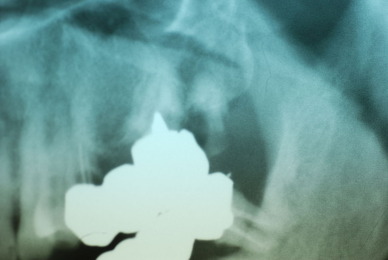

お口の中から差し歯、入れ歯、詰め物を追放しましょう!

口の中の病気を治し、病気を興さない医療を目指します。

「川崎市の入れ歯なら新丸子西口歯科医院へ」

「顎関節症は新丸子西口歯科医院へ」